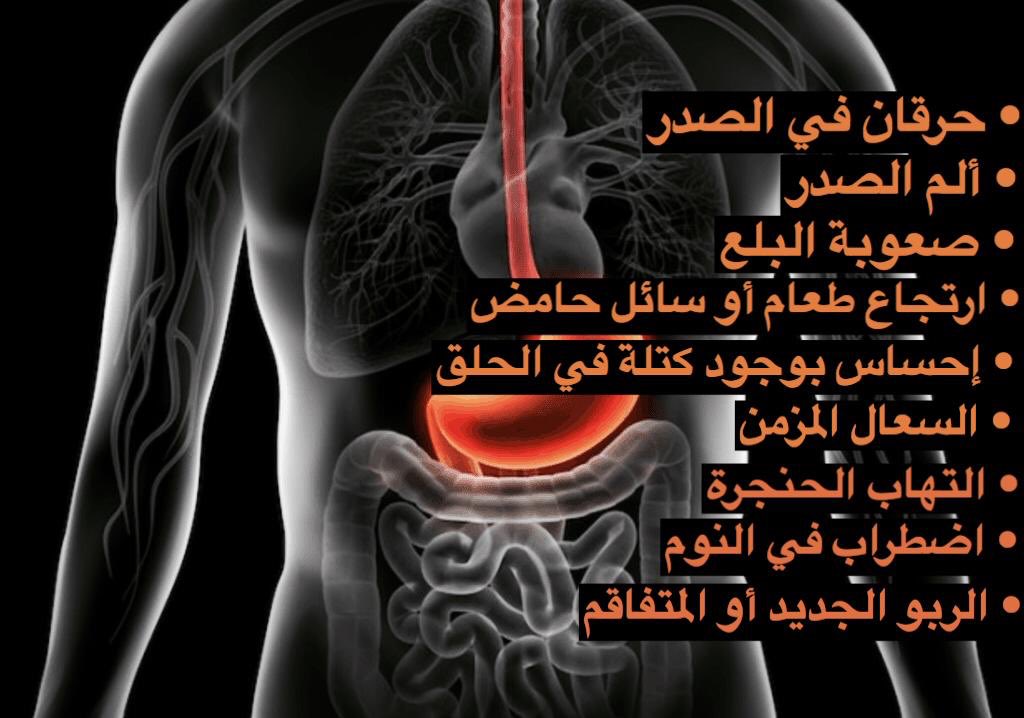

متى تزور الطبيب ؟ إذا كنت تعاني من ألم في الصدر، خاصة إذا كنت تشعر أيضًا بضيق في التنفس أو ألم في الفك أو الذراع